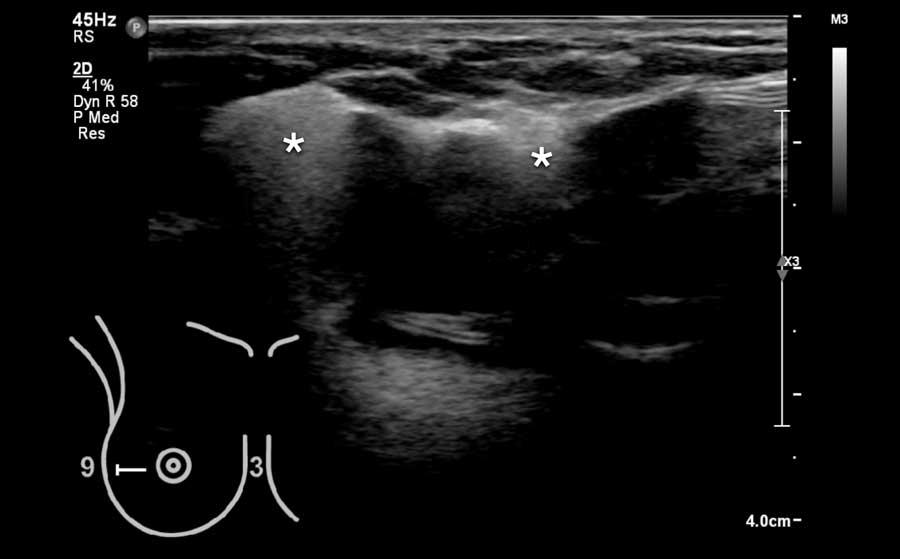

Hình ảnh siêu âm cho thấy một vùng tập trung mô tuyến nằm trong nền mô mỡ của vú.

Do mô tuyến có độ chắc hơn mô mỡ, vùng này sẽ có cảm giác như một khối khi sờ nắn.

Chụp nhũ ảnh được thực hiện với đánh dấu vị trí khối sờ thấy và cũng cho thấy hình ảnh tập trung khu trú của mô tuyến bình thường.